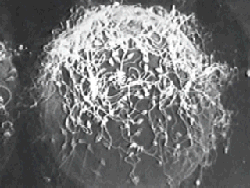

Сперматозоиды атакуют яйцеклетку. Зрелище фантастическое! Спермии синхронно бьют хвостами, заставляя яйцеклетку медленно вращаться против часовой стрелки. Внутрь попадет только один из них.